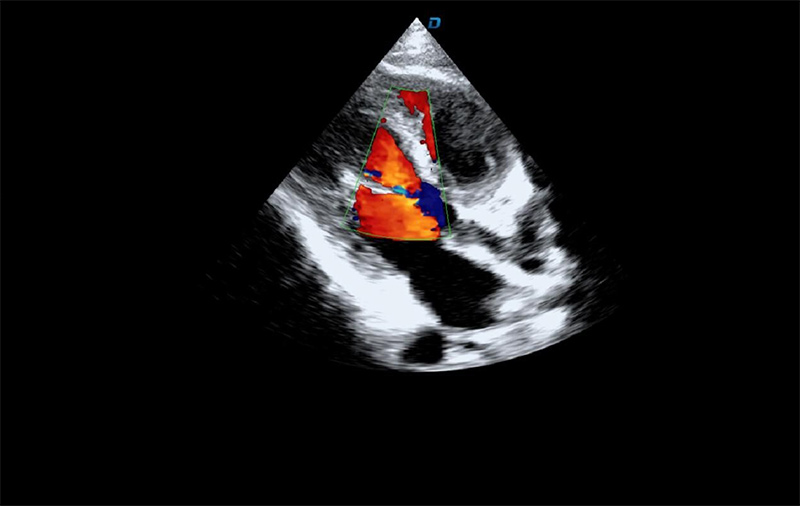

心臟彩超機檢查

有些心臟病會引起心臟電活動的改變,但是有些心臟的疾病卻不影響心電,而只影響心臟本身的結構。比如心臟擴大,心臟收縮無力,心臟的瓣膜關閉不嚴密,這些疾病的診斷及發現更多的依賴于心臟彩超,這些病變一般不隨癥狀的緩解而緩解。心臟超聲心動圖,不需要開胸,就可以看到心臟的大小、內部結構、瓣膜運動情況等。除了探頭壓迫可能會有疼痛或不適感外,對患者沒有任何創傷。

臨床上,心臟超聲心動圖主要用于對各種先心病、心臟瓣膜病的診斷;各種心肌病、心包疾病的診斷和心臟功能的評估。部分嚴重肺氣腫、胸廓畸形等患者,因為超聲圖像質量欠佳而診斷效果受到一定限制。